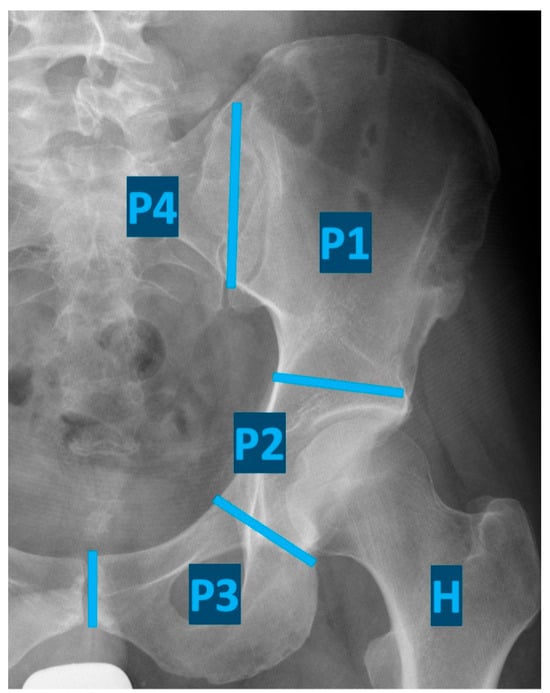

Potentially curative surgical intervention for musculoskeletal sarcomas involving the pelvic bones requires an internal hemipelvectomy, a highly complex procedure that must be individualized based on patient age, comorbidities, and tumor characteristics, including size, location, and histologic type. The extent of resection is classified according to the Enneking classification (Figure 1) [4,5]. In some patients, tumor infiltration of the hip joint and periarticular tissues necessitates the resection of the proximal femur. Pelvic reconstruction is likewise tailored to the individual patient, depending on patient characteristics and the extent of resection [6].

Figure 1. Classification of internal hemipelvectomies according to Enneking (resection of the iliac wing (P1), periacetabular region (P2), pubis and ischii (P3), sacrum (P4), and proximal femur (H)).